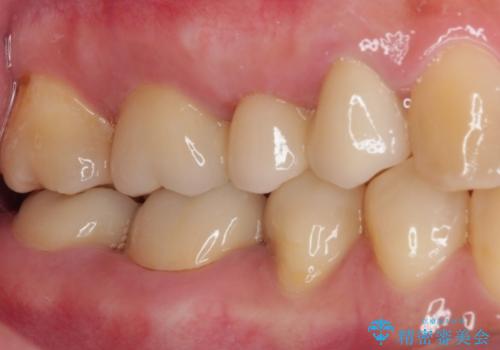

- 奥歯に問題が多くて困っているとのことで来院された患者様です。

開咬により奥歯のみが接触している状態で、前歯部にほとんど接触のない状態で、奥歯に非常に負担のかかる咬み合わせでした。

また、欠損や根管治療の必要な歯など、むし歯による問題も多く散見されました。

まずはむし歯の治療を行い、その後ワイヤー矯正にて咬み合わせを改善し、途中インプラント埋入を行い、矯正治療後に補綴治療を行うこととしました。